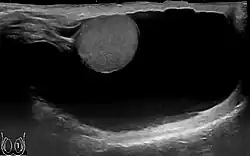

-

Communicating hydrocele, caused by the failure of the processus vaginalis closure.